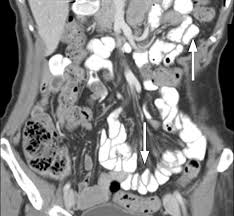

Το υγρό Gastrografin, το οποίο παράγεται από την εταιρεία Bracco Diagnostics Inc., χορηγείται σε ασθενείς με συμπτώματα ειλεού πριν από ακτινογραφία ή αξονική τομογραφία. Με αυτόν τον τρόπο, οι γιατροί μπορούν να δουν με ακρίβεια τη θέση και τη σοβαρότητα μιας πιθανής απόφραξης του λεπτού εντέρου, και να αποφασίσουν εάν απαιτείται χειρουργική παρέμβαση.